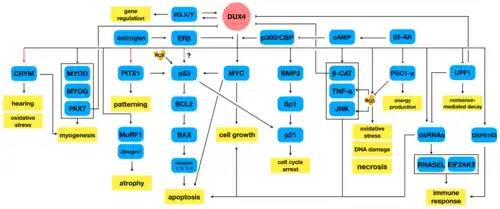

As of 2020, there seems to be a consensus that aberrant expression of DUX4 in muscle is the cause of FSHD.[75] DUX4 is expressed in minuscule amounts, detectable in 1 out of every 1000 immature muscle cells (myoblast), which appears to increase after myoblast maturation, in part because the cells fuse as they mature, and a single nucleus expressing DUX4 can provide DUX4 protein to neighboring nuclei from fused cells.[76]

How the DUX4 protein causes muscle damage remains an area of active research.[77] DUX4 protein is a transcription factor that regulates many other genes. Some of these genes are involved in apoptosis, such as p53, p21, MYC, and β-catenin, and indeed it seems that DUX4 protein makes muscle cells more prone to apoptosis. Other DUX4 protein-regulated genes are involved in oxidative stress, and it seems that DUX4 expression lowers muscle cell tolerance of oxidative stress. Variations in the ability of individual muscles to handle oxidative stress could partially explain the muscle involvement patterns of FSHD. DUX4 protein downregulates many genes involved in muscle development, including MyoD, myogenin, desmin, and PAX7, and indeed DUX4 expression has shown to reduce muscle cell proliferation, differentiation, and fusion. DUX4 protein regulates a few genes that are involved in RNA quality control, and indeed DUX4 expression has been shown to cause accumulation of RNA with subsequent apoptosis.[75] Estrogen seems to play a role in modifying DUX4 protein effects on muscle differentiation, which could explain why females are less affected than males, although it remains unproven.[78]

The cellular hypoxia response has been reported in a single study to be the main driver of DUX4 protein-induced muscle cell death. The hypoxia-inducible factors (HIFs) are upregulated by DUX4 protein, possibly causing pathologic signaling leading to cell death.[79]

Another study found that DUX4 expression in muscle cells led to the recruitment and alteration of fibrous/fat progenitor cells, which helps explain why muscles become replaced by fat and fibrous tissue.[76]

A single study implicated RIPK3 in DUX4-mediated cell death.[80]